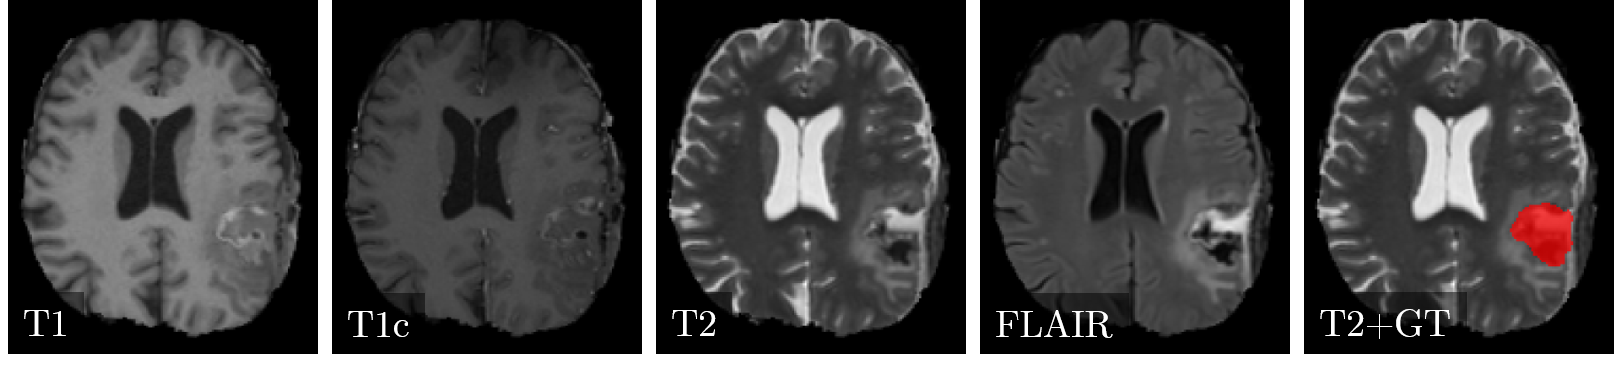

Clinical dataset.

Postoperative magnetic resonance images with 30 subjects to evaluate the post-operative (i.e., after tumor resection) status of glioblastoma patients are available. The images were acquired in the four standard sequences (T1-weighted (T1), T1-weighted post-contrast (T1c), T2-weighted (T2), and Fluid-attenuated inversion-recovery (FLAIR)). All sequences of a subject are co-registered and anonymized, i.e., skull-stripped. Three clinical radiation oncology experts with different levels of expertise (two years, four years, and over six years of clinical experience) created the label maps. These maps delineate the cavity after tumor resection and are used for radiotherapy planning. The difficulty of the task is associated with the presence of blood products, cerebrospinal fluid infiltration and air pockets, which change the appearance of the resection cavity. The dataset ground truth was created by a majority voting of the three expert segmentation. Figure 1 illustrates the four sequences and the ground truth in the dataset on an exemplary image slice.